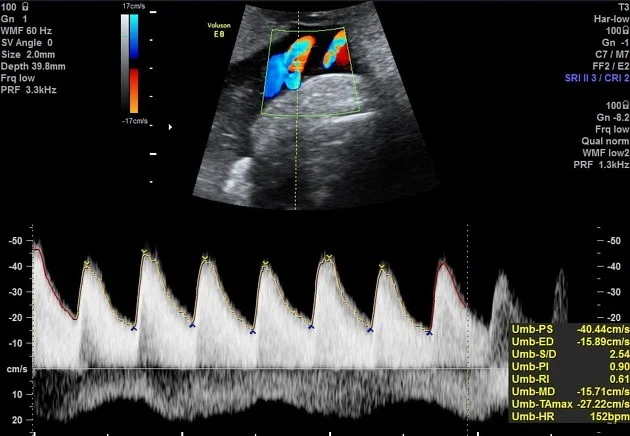

Umbilical Artery Doppler Ultrasound

- Umbilical artery Doppler: low, absent, or reversal of diastolic flow.

Progression of Umbilical Artery Doppler Changes

- Normal pregnancy

- Reduced end diastolic velocity

- Absent end diastolic velocity

- Reversed end diastolic velocity (Dexamethasone + Deliver now)